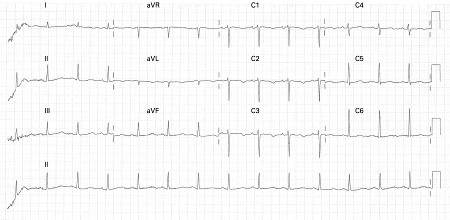

Careful attention must be given to the QT interval and the corrected QT interval (QTc). ECG findings associated with a high risk of life-threatening arrhythmias include T-wave alternans and functional 2:1 block.[5][Figure caption and citation for the preceding image starts]: ECG showing QT prolongation (QTc = 519 ms)Chong DW, Ankolekar SJ, McDonald J. BMJ Case Reports. 2009; doi:10.1136/bcr.01.2009.1426 [Citation ends].

The QT interval is the ECG representation of ventricular depolarisation and subsequent repolarisation and may be measured in any lead in which it looks prolonged.[Figure caption and citation for the preceding image starts]: ECG showing QT prolongation (QTc = 519 ms)Chong DW, Ankolekar SJ, McDonald J. BMJ Case Reports. 2009; doi:10.1136/bcr.01.2009.1426 [Citation ends].

LQT1 is characterised by prolonged QT intervals associated with a broad-based T wave.[16][Figure caption and citation for the preceding image starts]: ECG findings in type 1 long QT syndromeFrom the collection of Dr James P. Daubert [Citation ends].